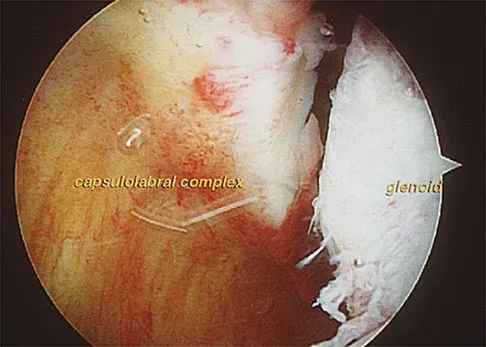

A 51-year-old male truck driver has had progressive left hip pain for more than 2 years, and he reports that the pain has become severe in the past 9 months. He is now unable to work because of the pain. Examination reveals that range of motion of the hip is limited to 95 degrees of flexion, 0 degrees of internal rotation, and 20 degrees of external rotation. The plain radiograph, MRI scan, and intraoperative gross photographs are shown in Figures 9a through 9d. Management should consist of